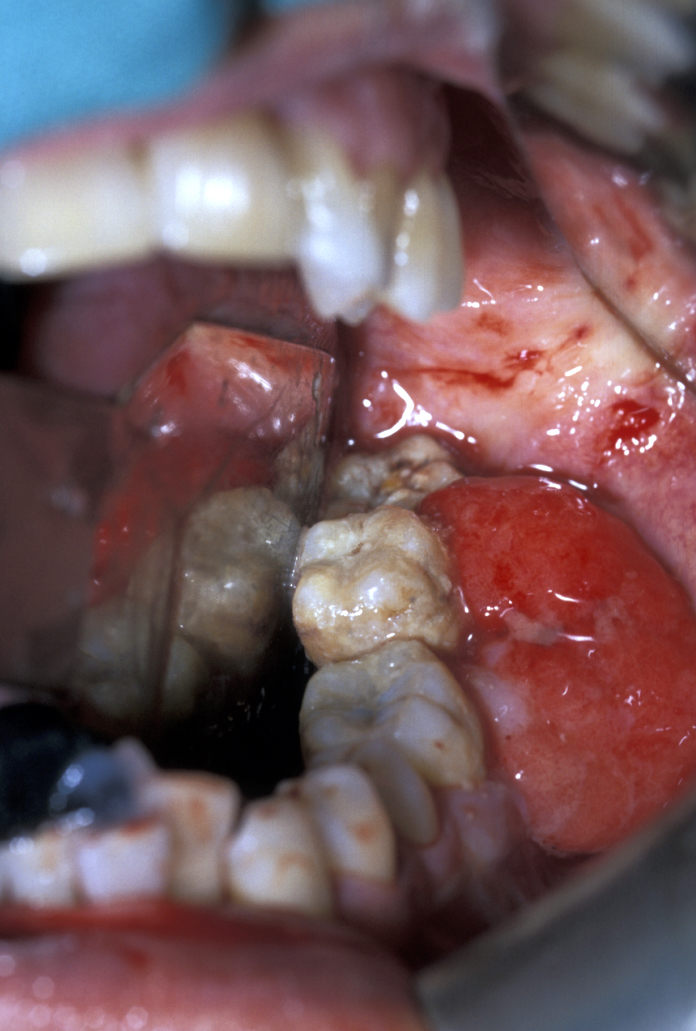

Brown tumour of hyperparathyroidism

This is a giant cell lesion which can look extremely florid (reddish) and mandates early biopsy for diagnosis. It occurs secondarily to hyperparathyroidism (overactivity of the parathyroid gland), but this diagnosis is usually made only after biopsy of the lump (either incisional or excisional) when the findings of giant cells in a fibrous stroma (scarred connective tissue) mandate an assessment of bone biochemistry and measuring parathyroid hormone levels (PTH blood test).